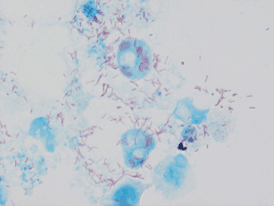

![]() Rickettsia conorii | |

Возбудителем инфекции является бактерия Rickettsia conorii, которая паразитирует внутриклеточно и внутриядерно. Как правило, она обладает размерами 0,3—0,8 мкм и с точки зрения патогенеза представляет опасность для кроликов, морских свинок, сусликов, обезьян, белых мышей и белых крыс. У самцов этих животных она может быть выявлена в клетках мезотелия и служить причиной периорхита. У заболевших людей присутствие возбудителя возможно обнаружить в крови во время первых суток лихорадочного периода, в розеолах кожи и в первичном аффекте, который неизбежно возникает в месте укуса клеща[3]. Морфологические, тинкториальные и иммунологические свойства бактерии Rickettsia conorii имеют много сходного с Rickettsia rickettsii, которая является возбудителем другой опасной болезни — пятнистой лихорадки Скалистых гор[6].